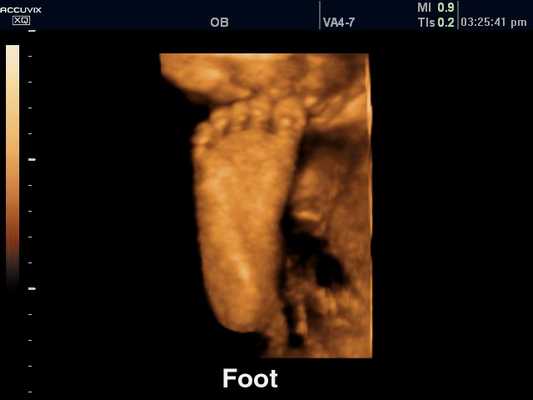

Позвоночник плода, 3D

[EN] Эхограмма №316: Позвоночник плода в режиме 3D.

Изображение получено с помощью УЗ сканера Accuvix-XQ (снят с производства).